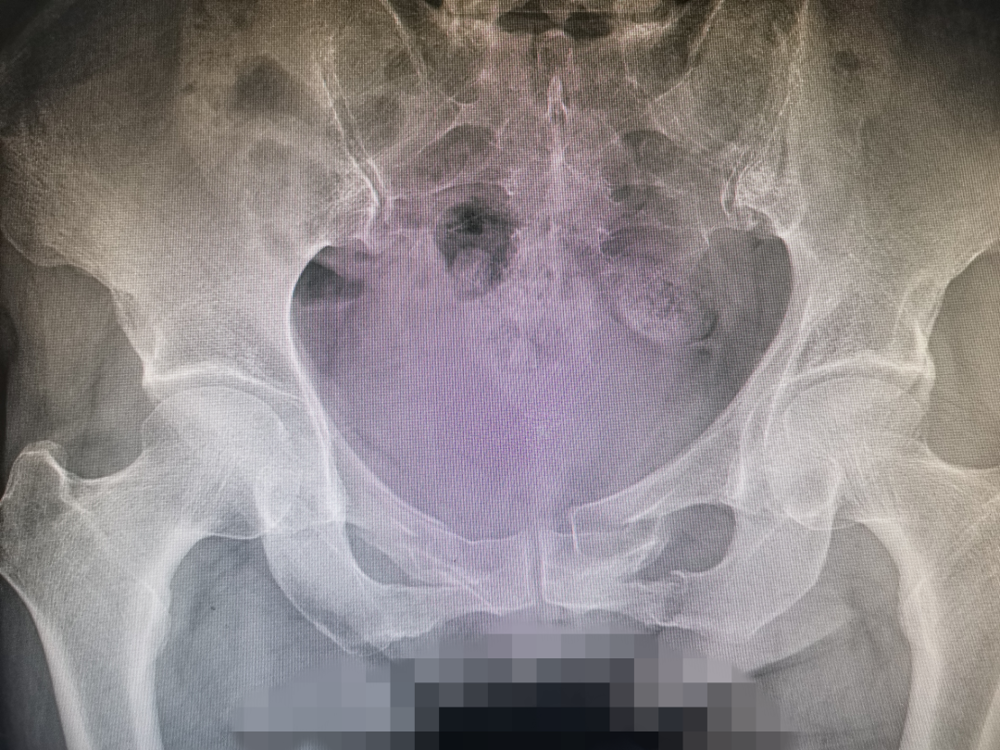

患者葉女士,因不慎摔倒導致(zhì)全身多處疼痛入院,完善檢查顯示雙側恥骨(gǔ)上下肢骨折,骨盆前環不穩(wěn)定。對(duì)於骨盆(pén)前環骨折的治療,保(bǎo)守治療需長期臥(wò)床,易導致褥瘡、肺部感染、泌尿係感染及深靜(jìng)脈血栓風險;傳統開放複位鋼板(bǎn)內固(gù)定術式手術切口大、手術時間長,同時存在膀胱的醫源性損傷風險。尤其對於肥胖患者,外固定架及其它內(nèi)固定術(shù)式比較困難,風險相對較大,且會給患者(zhě)的生活帶來極大不便。